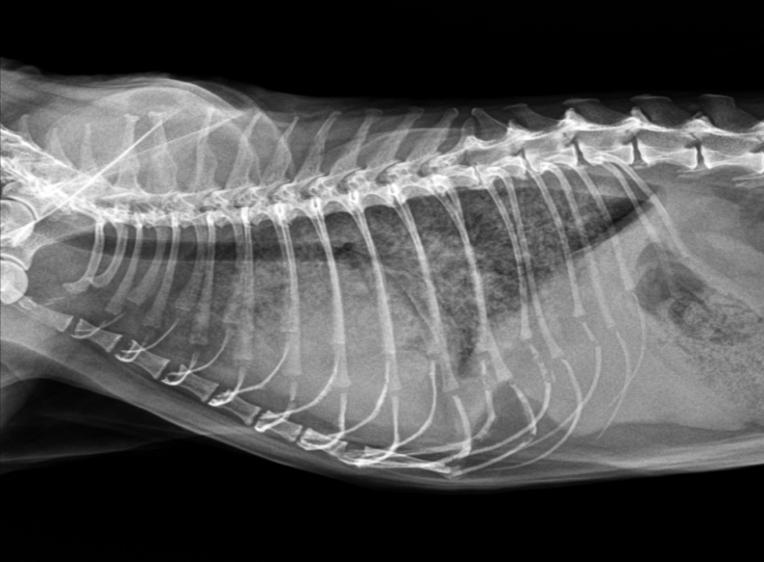

临床检查:精神状态尚可,鼻头湿润,粘膜偏紫,四肢冰凉,四肢脚垫颜色深紫色,耳道皮肤检查无异常,体表淋巴结未见异常,心音异常,肺音正常,眼观腹式呼吸。腹部触诊空虚,BCS3/9,CRT>2S,肛周清洁。

DR显示肺水肿

心脏彩超显示心包积液

全心衰竭

经过一周的治疗,小于的肺部积水逐渐消失,呼吸频率比之前缓解了很多,开始吃东西。

继续按上述方案治疗一周后,肺部积水几乎完全消失,呼吸恢复正常,四肢脚垫颜色由黑紫色恢复到粉色,食欲恢复正常,排尿排便正常。

治疗两周后,呼吸异常基本消失,恢复日常生活。